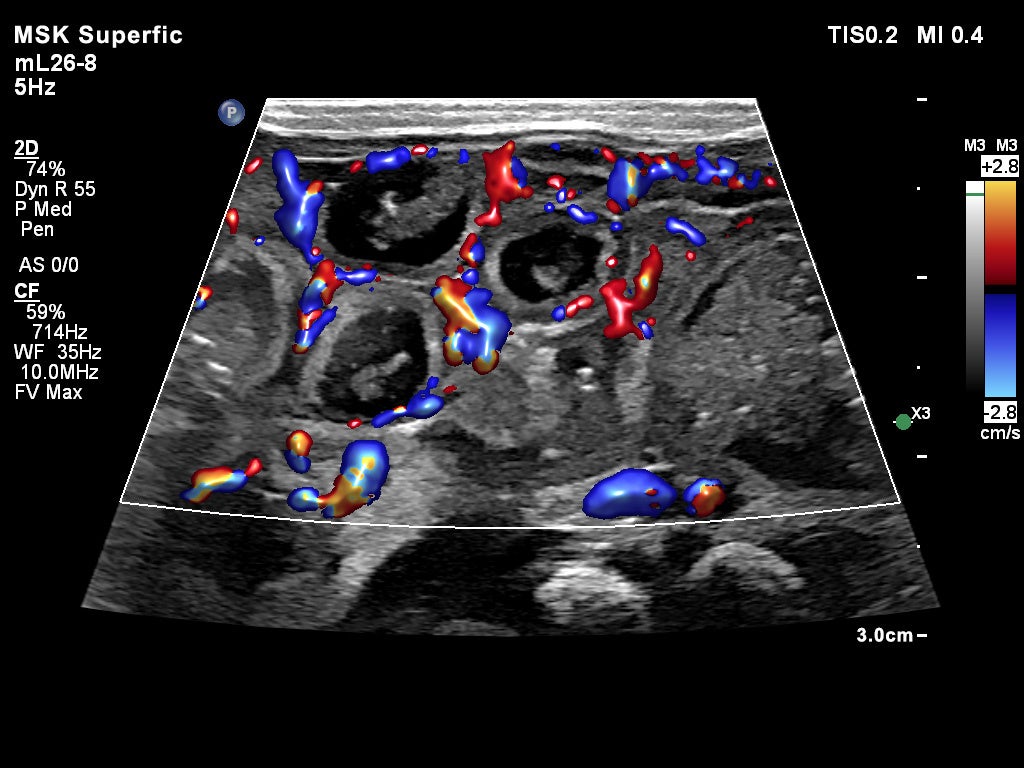

血流情報を詳細に観察するため、微細な血流を表示するMicro Flow Imaging (MFI)とMFI HD、そして新しい血流表示のFlow Viewerに対応し、臨床的に価値のある画像を提供します。穿刺の際には、針の視認性を向上するNeedle Visualizationモードにも対応しており、トランスジューサヘッドには4つのセンターマーカーが記されているため、穿刺の際の位置決めに役立ちます。

mL26-8画像 腸管(カラー・Flow Viewer)